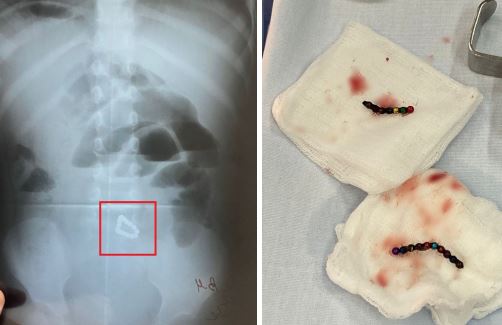

В Уфе хирурги больницы скорой помощи спасли 2-летнюю девочку, проглотившую 17 магнитных шариков, сообщили в Минздраве Башкирии.

Девочка поступила к медикам с жалобами на вялость и частую рвоту. Рентген-снимок показал наличие магнитных шариков от конструктора в кишечнике пациентки. Родители девочки не подозревали, что она их проглотила.

«Соединившись между собой в разных отделах кишечника, шарики спровоцировали его непроходимость и образование кишечных свищей. Хирурги сумели постепенно извлечь из кишки все инородные тела, а затем зашили три отверстия, проделанных магнитиками», - сообщили в министерстве.